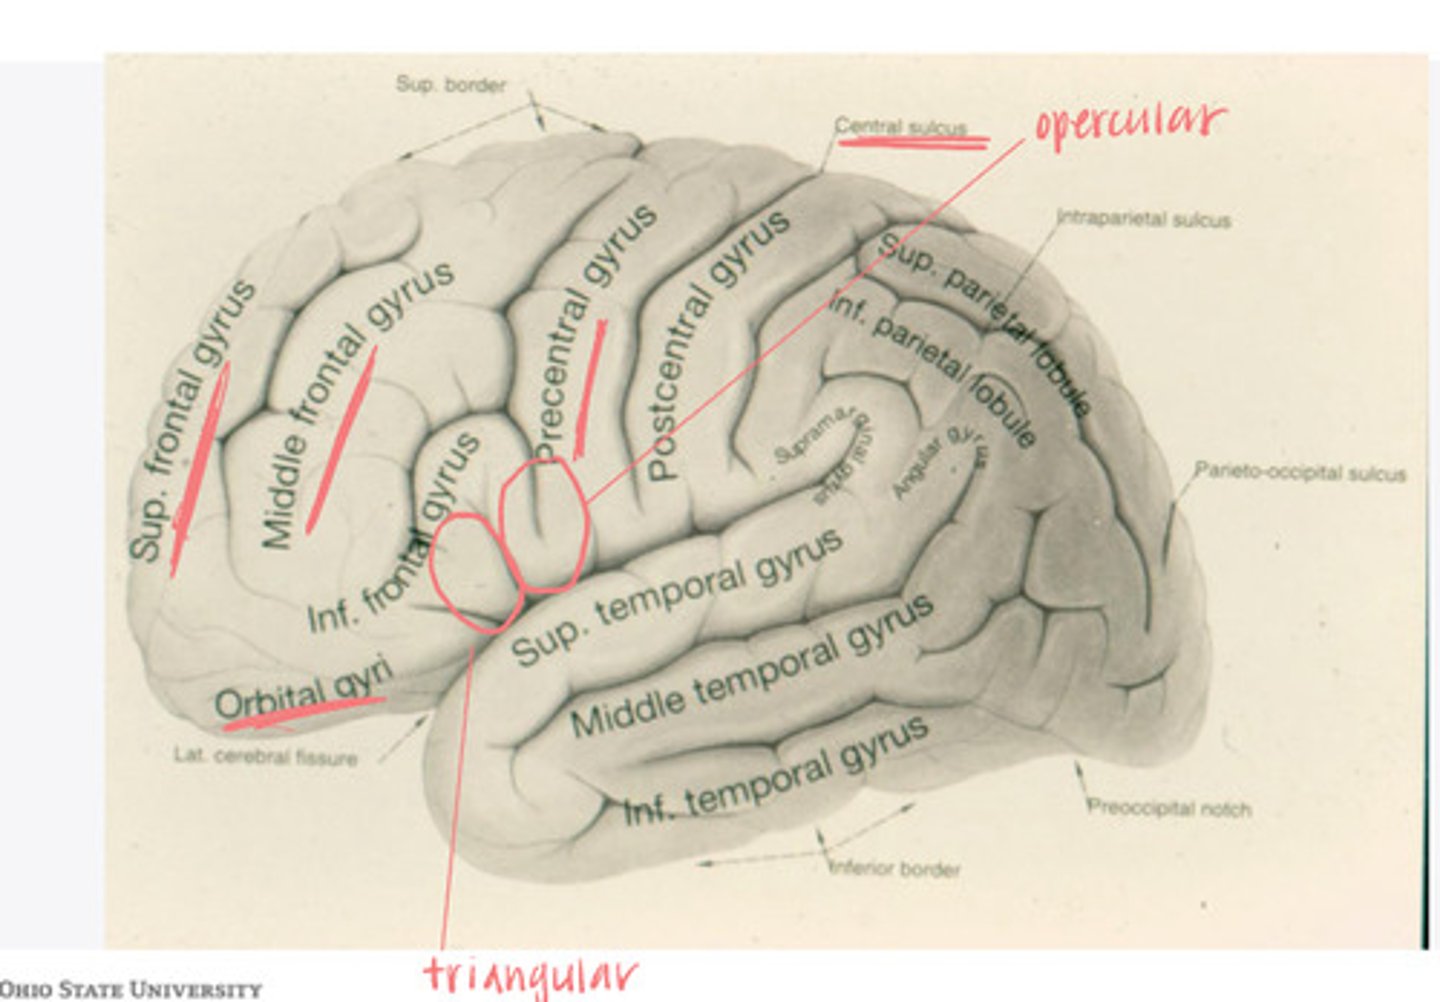

The frontal lobe is divided into what 4 gyri?

-opercular

-triangular

-orbital gyrus

What are the 3 divisions of the inferior frontal gyrus?

-post-central gyrus

-superior parietal lobule

-inferior parietal lobule

What are the divisions of the parietal lobe?

-supramarginal gyrus

-angular gyrus

What are the divisions of the inferior parietal lobule?

-superior temporal

-inferior temporal

What are the 2 major sulci of the temporal lobe (on lateral view)?

-superior temporal

-middle temporal

-inferior temporal

What are the 3 major gyri of the temporal lobe (on lateral view)?